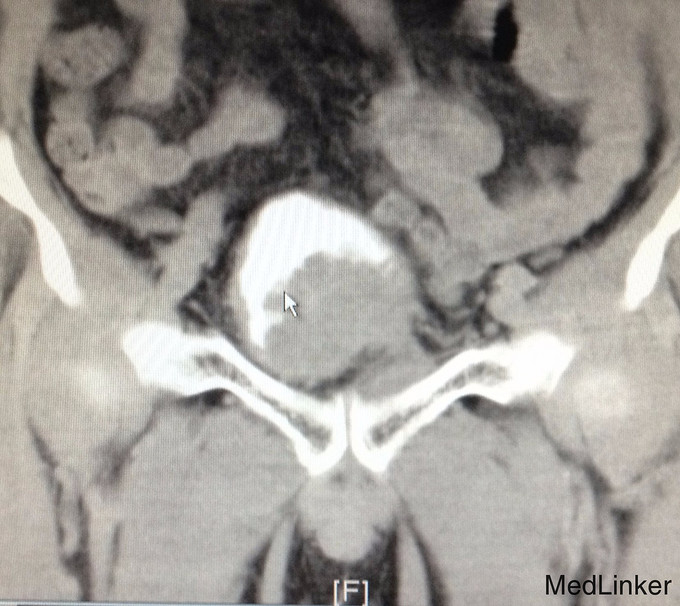

查体:右侧腋窝及右侧锁骨上可触及淋巴结肿大,质硬,移动度差。双侧睾丸缺如。 辅助检查:我院CTU提示膀胱癌,侵犯前列腺及左侧输尿管下段,可疑侵犯右侧精囊腺。